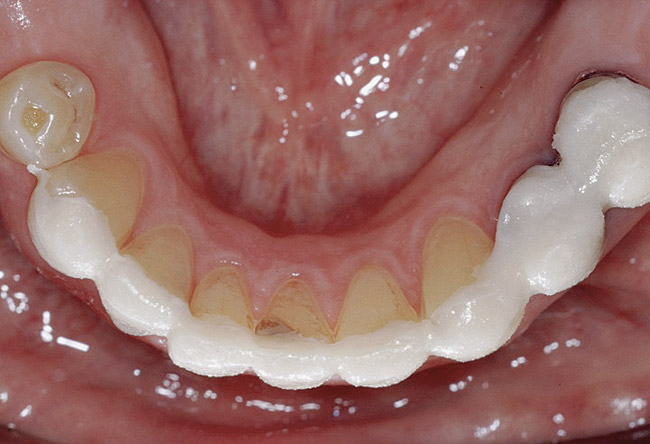

Figure 6. The patient is congenitally missing the maxillary lateral incisors and canines and all lower incisors and canines, causing concerns about esthetics. The maxillary laterals and canines and mandibular canines have been bonded with composite.

Figure 6

Figure 7. The mandibular incisors are loose, and No. 25 has recently been lost.

Figure 7

Figure 8. The lower one third of face seems shortened and the upper lip is not well supported and appears thin.

Figure 8